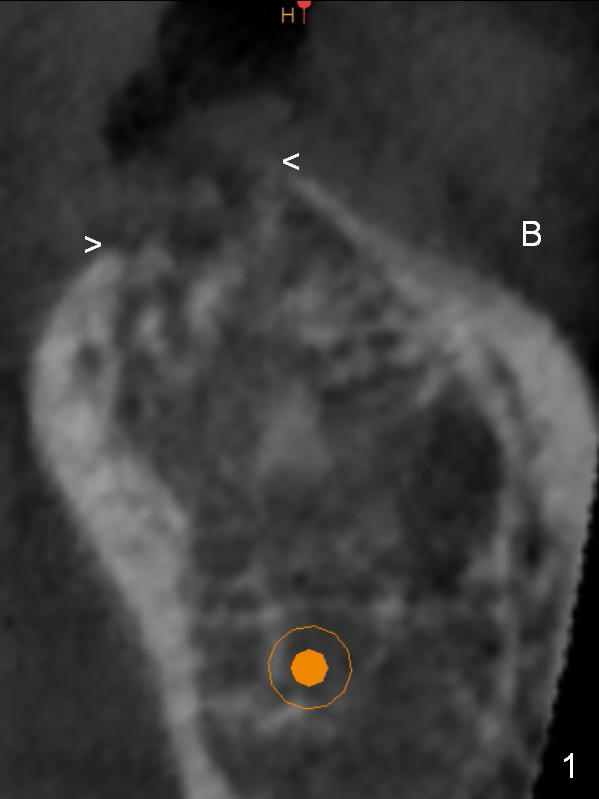

Preop palpation of the edentulous area at #18 does not show the flatness of the ridge top as shown by CBCT.  Incision reveals that the ridge is not as wide as CBCT indicates (Fig.1 (coronal section) between arrowheads).  In fact the ridge is concave (Fig.2 red dashed line).  Osteotomy is initiated in the middle of the concavity (Fig.2 green line) with insertion of 7 mm guide pin (Fig.3).   After removal of the pin, the osteotomy is moved buccally (Fig.4).  After Marking Bur and 4.3 mm Magic Drill, a 5x9 mm IBS implant is placed with 2.8 mm clearance from the Inferior Alveolar Canal (Fig.6).  Following deepening the osteotomy with Final Drill, the implant is placed deeper (Fig.7).  The osteotomy happens to be established in the mesial socket, since the distal socket has not completely healed (Fig.6 yellow dashed line).  Granulation tissue is removed.  Since the lingual crest is lower than the buccal one (Fig.1 B), there is lingual thread exposure after implant placement (Fig.5).  The exposed thread is covered by bone graft (autogenous bone, allograft and Osteogen, Fig.5 pink circles).  Some of the graft is apparently pushed into the distal socket (Fig.7 yellow dashed line) post GBR and suture.  As the implant is placed twice, insertion torque is <10 Ncm (although the implant is stable).  A 5x3 mm healing abutment is placed (Fig.7 H).